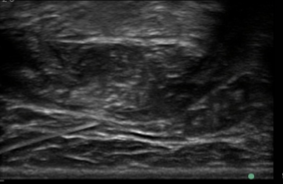

EMG for Localisation

- The importance of targeting the motor endplate has been emphasised in animal models.

- Proximity to endplate will increase the speed of uptake and degree of terminal saturation and the ultimate effectiveness of the toxin.

- Using rat anterior tibialis muscle, Shaari and Sanders demonstrated that toxin injection into the motor endplate region produces the greatest paralysis. Injections only 0.5 cm away from the region resulted in a 50% decrease in paralysis.